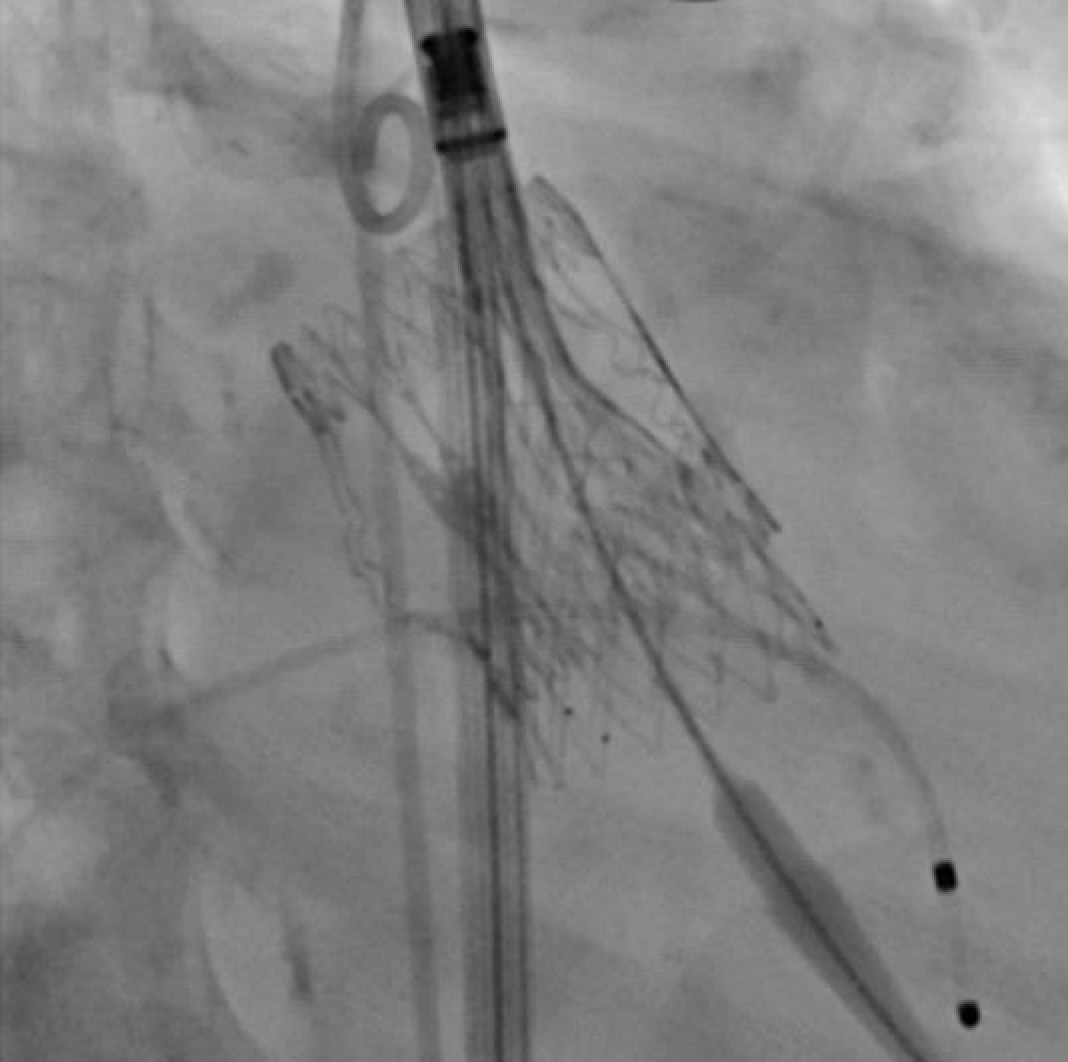

As some have identified, this valve was in-folded. We successfully retrieved the valve and put in a new one. I want to expand on this issue a bit. 🧵

Would you release this 34 mm Evolut? Why or why not? @GuiAttizzaniMD @djc795 @akcmahi